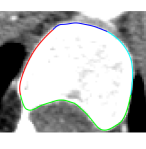

We consider a axial X-ray CT slice of a human lumbar vertebra (see Figure 5(a)). First, we apply an edge detection technique, to detect the set of edge points. In this specific example, we adopt the Canny edge detector [42], others methods could be applied too. We select a bounding box for the point cloud, which is then partitioned in smaller sub-regions (see Figure 5(b)). Lastly, we apply our technique to each sub-region to obtain a global approximation (see Figure 5, right). Here, a -NN weight is set as the number of points is relatively small. Uniform knot vectors are considered as they produce reasonable approximations. The number of B-splines is chosen, in each sub-region, by a Leave-One-Out cross-validation [36]. Interpolating conditions are imposed at the boundaries in order to have a more natural continuity (see Figure 5(c)). Notice that the shape of the vertebra is correctly preserved in the passage from the image to the final approximation.

|

| (a) | (b) | (c) |

Table 1 reports the values of the parameters and that best approximate the original curve segments and the corresponding error measures for the wQISA approximations.

| Lumbar Vertebra | Left Eye | Right Eye | ||||||

| V1 | V2 | V3 | V4 | LE1 | LE2 | RE1 | RE2 | |

| sample size | 82 | 38 | 30 | 38 | 422 | 730 | 428 | 638 |

| 20 | 6 | 8 | 7 | 12 | 12 | 8 | 12 | |

| 5 | 5 | 5 | 5 | |||||

| MAE | 0.656 | 0.3323 | 0.278 | 0.292 | 0.025 | 0.052 | 0.025 | 0.043 |

| RMSE | 0.898 | 0.418 | 0.378 | 0.379 | 0.030 | 0.074 | 0.030 | 0.079 |

| Jaccard | 0.988 | 1.000 | 1.000 | 1.000 | 0.995 | 1.000 | 1.000 | 1.000 |

| Hausdorff | 0.014 | 0.016 | 0.011 | 0.012 | 0.010 | 0.021 | 0.017 | 0.041 |